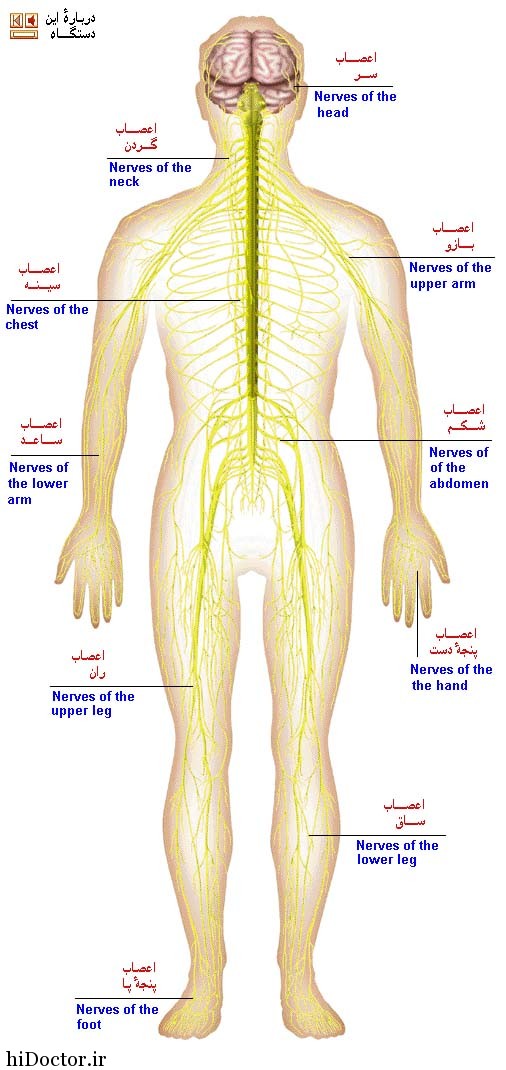

شکل دوم شکم مادری را نشان می دهد که جنین دختر دارد. وحشت مادر از عکس سونوگرافی جنین داخل شکمش عکس. تصاویر جالب از داخل مغز و نخاع انسان آخرین نیوز. بدن انسان کل ساختار انسان است که سر گردن تنه سینه و شکم دو بازو و دست ها و دو ساق پا و پاها را شامل می شود.